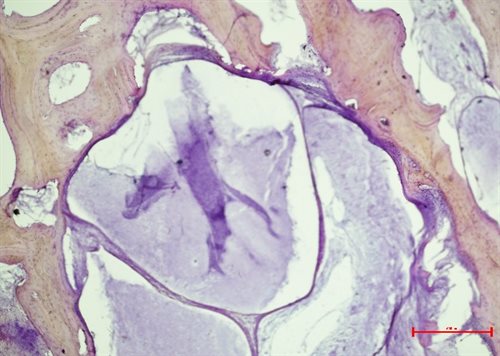

An MRI scanner was used to find BMLs inside the tibia from the bone just below the knee in 10 osteoarthritis subjects. Samples were taken of the tissues from within the bone, and samples from BML regions were compared to regions without BMLs. Laboratory analysis, using chemical stains and microscope-based investigations were used to look at what was found within a BML.

We previously found that BMLs were small regions that often contained inflammation, scarring, thickened bone, extra blood vessels, cysts, and newly formed cartilage. We were able to devise a simple scoring system based on anatomical features of BMLs that could be used for future research projects to assess BMLs in joint tissues. We tested this scoring system on 163 samples with and without osteoarthritis and found that measuring the anatomical features of BMLs is a useful tool for future research. We also found nerves growing within the BMLs which might be the cause of some osteoarthritis knee pain.